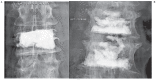

Percutaneous vertebroplasty (PVP) is a minimally invasive procedure to treat back pain secondary to osteoporotic vertebral compression fractures (VCF). This study aims to review our techniques and outcomes in patients with VCF. Outcomes of all patients who underwent PVP at our institution from 1998 to 2014 were retrospectively collected from medical records and follow-up telephone interviews. 1174 PVP procedures for VCF in 673 patients were identified to have complete follow-up data. Patients with inadequate data were excluded from the analysis. Procedural aspects such as unipedicular or bipedicular access, vertebral region treated, amount of cement injected into vertebrae, number of levels treated at a single session, refracture rates and location, presence of a necrotic cavity, and pain outcomes were examined. Excellent rates of improvement of back pain for both single level and multilevel PVP were achieved in 92% of patients. Unipedicular or bipedicular approach, cement volume, vertebral region treated, cement extravasation, and presence of a necrotic cavity did not affect pain outcomes or refracture rates. Fractures that did develop after PVP were often adjacent and occurred earlier than distant level fractures. Lumbar vertebrae required more cement than thoracic vertebrae. PVP provides excellent rates of pain relief in both single and multilevel procedures. The procedural aspects evaluated did not affect pain outcome or refracture rates. Adjacent refractures tended to occur sooner than distant ones.